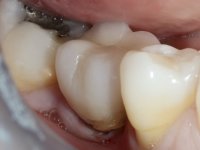

Segunda Fase.

Após 5 anos da primeira intervenção, a paciente surge na consulta com uma peri-implantite nos implantes colocados no local dos dentes 1.2 e 4.6. Começamos por abordar a peri-implantite no local do dente 2.2. Foi feita uma ponte provisória de laboratório em acrílico com 2 elementos. O dente 1.1 como pilar e o 1.2 como pôntico, este último apresentava um apoio distal. A coroa do 1.2 foi removida do coto com um corte longitudinal feito com turbina e depois foi fraturada com um mini luxador. O coto foi de seguida desaparafusado do implante. Fez-se o mesmo procedimento para remover a coroa do 1.1. O dente 1.1 foi re-preparado e a ponte provisória foi rebaseada em boca com acrílico autopolimerizável. Feito o correto acabamento e polimento da provisória foi feita a sua cimentação temporária com cimento de policarboxylato. Numa consulta posterior. foi feita a remoção da ponte provisória, feita a cirurgia para explantação do implante, colocou-se um novo implante e fez-se a regeneração óssea da zona com uma membrana não reabsorvível. 3 meses após foi removida a coroa do implante colocado no 4.6. Foi feito um corte horizontal com turbina na zona cervical e com um mini luxador descolou-se a coroa do coto. Após este procedimento fez-se a explantação do implante. Após 6 meses foi colocado um novo implante no local do 4.6. Após a osteointegração foi feita a impressão com a técnica de moldeira aberta e foi confecionada em laboratório uma coroa aparafusada sobre o implante. Aprovada pela paciente foi apertada definitivamente em boca. Após 1 mês removemos a ponte provisória antero-superior, reforçamos o dente 1.1 com um poste intra- radicular e reconstruimos o coto com uma resina de polimerização dual. Nessa mesma consulta expomos o implante colocado no 1.2 e fizemos uma impressão pela técnica de moldeira aberta com silicone de dupla viscosidade e presa rápida. No laboratório foi feita uma ponte provisória de 2 elementos, aparafusada sobre o implante e cimentada sobre o dente. A primeira ponte provisória foi removida e colocada a segunda aparafusada sobre o implante. A linha de acabamento cervical do 1.1 foi rebaseada com resina composta durante o aperto do parafuso do implante. Depois foi removida, foram feitos os acabamentos e finalmente apertada sobre o implante e cimentada temporariamente sobre o dente. Após 2 meses de maturação dos tecidos moles em função do perfil de emergência criado pela nova ponte provisória, pudemos avaliar a estética conseguida em conjunto com a paciente. Neste longo processo o dente 2.1 teve que fazer um tratamento endodôntico. Decidiu-se assim fazer também uma coroa no dente 2.1.O dente 2.1 foi preparado na mesma consulta em que se fez a impressão ao implante. A ponte provisória foi utilizada para individualizar a peça de transferência, copiando o seu perfil de emergência e em seguida foi realizado o afastamento gengival com caolino. A impressão foi feita com a técnica de moldeira aberta com silicone de dupla viscosidade e presa rápida. Após a escolha da cor, a impressão foi enviada  para o laboratório onde foram confecionadas 2 coroas  com infraestrutura em Zr. revestidas a cerâmica para os dentes 1.1 e 2.1 e uma coroa aparafusada sobre o implante no dente 1.2. O trabalho final foi aprovado pela paciente e foi colocado definitivamente em boca. A coroa sobre o implante foi aparafusada com 35 N e as coroas foram cimentadas com cimento de ionómero de vidro reforçado com resina.